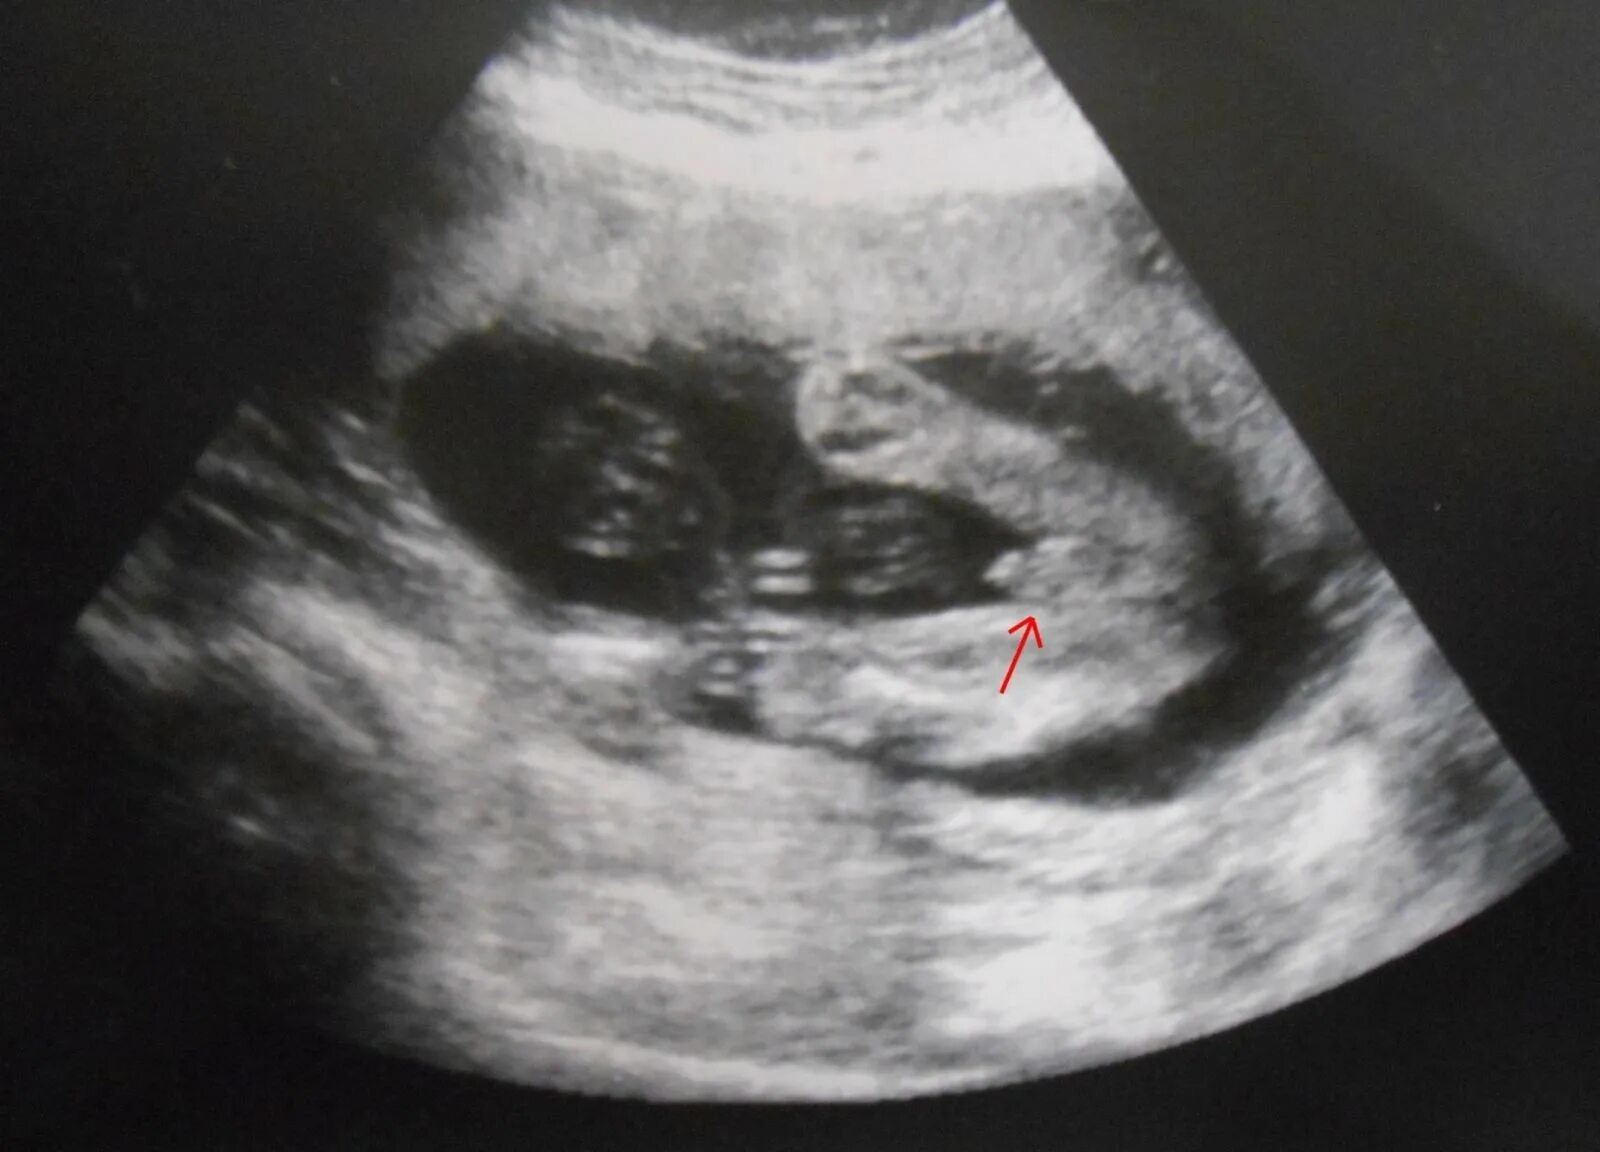

Как на узи выглядит мальчик и девочка